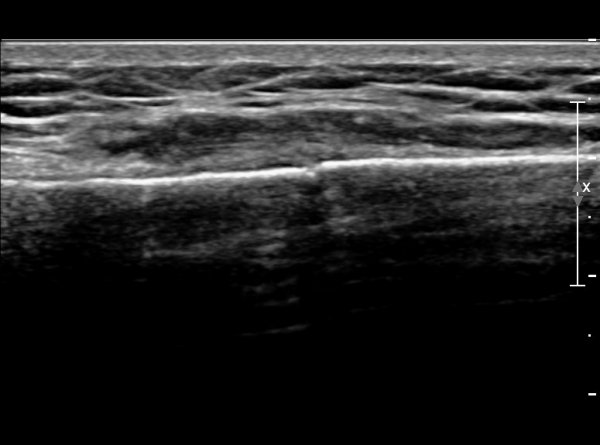

ŽÃËÀÚ¸¦ ¾à°£ ¸»´ÜÀ¸·Î À̵¿ÇÏ´Ï ¿¬ºÎÁ¶Á÷ ºÎÁ¾ÀÌ ´õ¿í ½ÉÇÏ°Ô °üÂûµÇ°í(»çÁø 2),